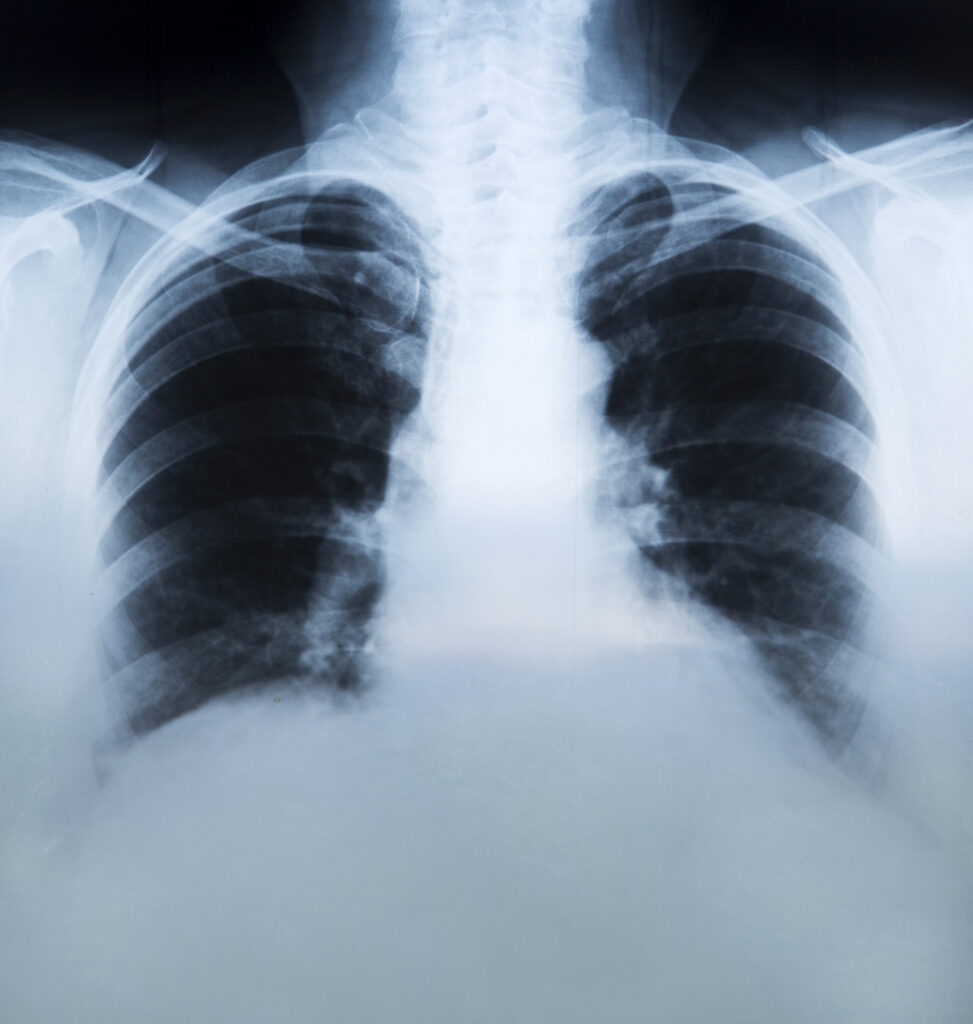

जहरीली हवा का खौफनाक सच: प्रदूषण से फेफड़ों में बन रहे कोरोना जैसे पैच, CT-Scan में दिखे चौंकाने वाले निशान। बढ़ते वायु प्रदूषण का सीधा असर अब फेफड़ों पर दिखने लगा है। डॉक्टरों के अनुसार CT-Scan में कोरोना काल जैसे पैच नजर आ रहे हैं, जो गंभीर स्वास्थ्य खतरे की ओर इशारा करते हैं।

देश के कई बड़े शहरों में जहरीली होती हवा अब सिर्फ आंखों में जलन या गले की खराश तक सीमित नहीं रह गई है, बल्कि इसका सीधा और गंभीर असर इंसानी फेफड़ों पर देखने को मिल रहा है। डॉक्टरों और रेडियोलॉजिस्ट्स का कहना है कि हाल के महीनों में किए जा रहे CT-Scan में फेफड़ों के अंदर ऐसे पैच दिखाई दे रहे हैं, जो कोरोना संक्रमण के दौरान देखे गए निशानों से काफी हद तक मिलते-जुलते हैं। यह खुलासा स्वास्थ्य विशेषज्ञों के लिए भी चिंता का बड़ा कारण बन गया है।

लगातार प्रदूषित हवा में सांस लेने से फेफड़ों में सूजन, संक्रमण जैसी स्थिति और टिश्यू डैमेज बढ़ रहा है। खासकर दिल्ली-NCR, उत्तर भारत और औद्योगिक क्षेत्रों में रहने वाले लोगों में यह समस्या अधिक देखने को मिल रही है। डॉक्टरों का कहना है कि कई मरीज ऐसे हैं, जिन्हें कभी कोरोना नहीं हुआ, फिर भी उनके CT-Scan में ग्राउंड ग्लास ऑपेसिटी (GGO) जैसे पैच नजर आ रहे हैं, जो आमतौर पर कोविड संक्रमण के दौरान देखे जाते थे।

रेडियोलॉजिस्ट बताते हैं कि CT-Scan में दिख रहे ये पैच किसी एक दिन की समस्या नहीं हैं, बल्कि महीनों तक प्रदूषण के संपर्क में रहने का नतीजा हो सकते हैं। यह स्थिति खासतौर पर बुजुर्गों, बच्चों, अस्थमा और पहले से फेफड़ों की बीमारी से जूझ रहे लोगों के लिए बेहद खतरनाक साबित हो रही है। डॉक्टरों का मानना है कि अगर समय रहते इस पर ध्यान नहीं दिया गया, तो आने वाले वर्षों में क्रॉनिक लंग डिजीज के मरीजों की संख्या तेजी से बढ़ सकती है।